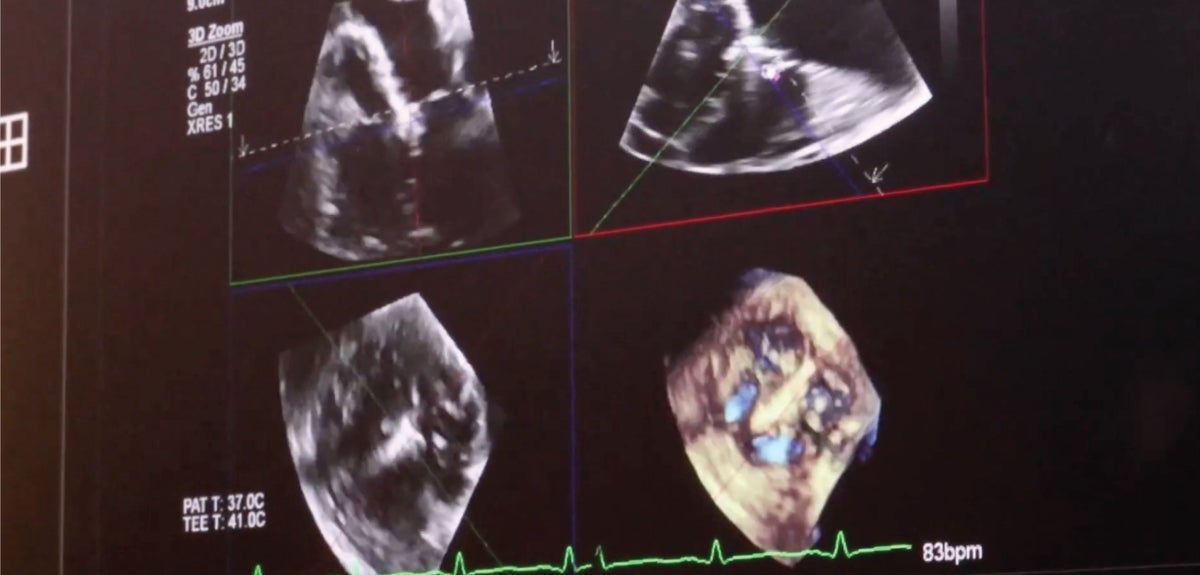

Sonographers and physicians at Saint Agnes are getting the whole story of the heart—with every beat—by using a pioneering 4D cardiac ultrasound system for patients with heart abnormalities. Saint Agnes is the first in the Valley with a 4D state-of-the-art transesophageal echo (TEE) ultrasound probe with full-color imaging, allowing for better visualization of heart anatomy during routine diagnostic exams and cardiac interventions and procedures.